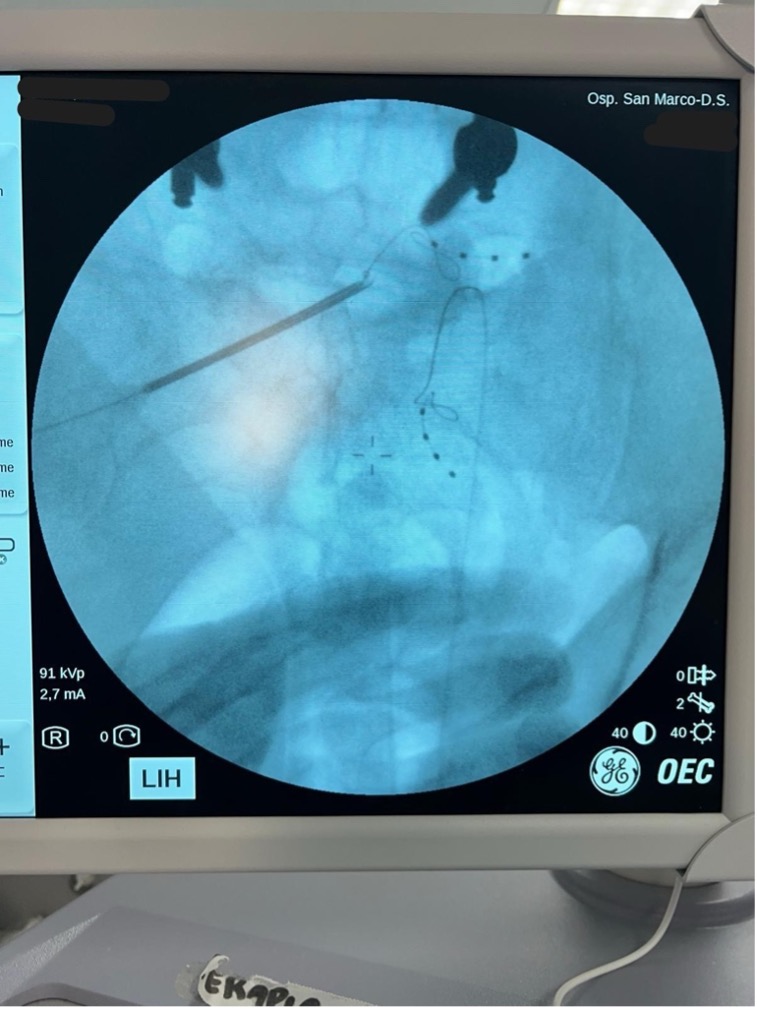

EFFICACY OF DORSAL ROOT GANGLION STIMULATION AFTER FAILURE OF SPINAL CORD STIMULATION IN PERSISTENT SPINAL PAIN SYNDROME TYPE 2: A CASE REPORT

S. Zappalà1, S. Stimolo1, G. Ruggieri1, A. Spina2, S. Caramma1 | 1Pain Center, Catania; 2Anesthesiology and Resuscitation, “G. Rodolico-S. Marco” University Hospital, Catania